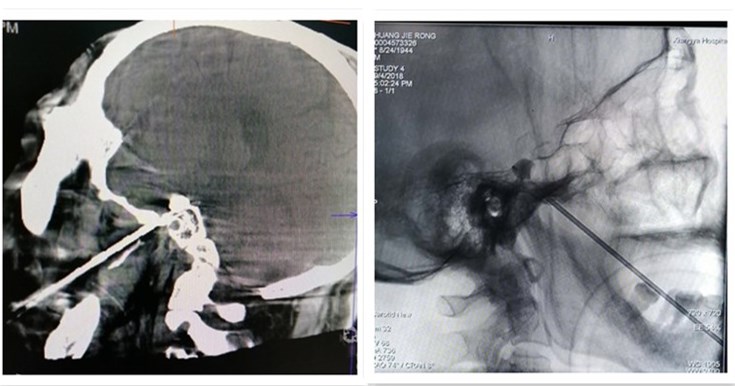

经过术前精心准备,疼痛诊疗团队任飞副教授、白念岳副教授、杨胜辉副教授以及罗剑刚博士加班为这两位患者进行了微创手术。在CT下定位卵圆孔,穿刺成功后,置入微球囊,然后扩张微球囊对半月节进行压迫。术后两位患者都诉面部疼痛消失,疼痛VAS评分由术前的6~7分降至术后0分,患者非常满意。

鄢建勤教授介绍,三叉神经痛是常见的头面部疼痛,以一侧面部三叉神经分布区内反复发作的阵发性剧烈痛为主要表现。目前三叉神经痛治疗方法包括微血管减压术、微球囊压迫术、射频毁损术和伽马刀治疗。根据患者不同的病因和身体情况可以选择不同的治疗方式。三叉神经半月节微球囊压迫术(PBC)是在影像介入下经皮穿刺到卵圆孔,将微球囊导管置人Meckel's囊,压迫半月神经节来治疗三叉神经痛。其相对于射频热凝术,可减少手术痛苦、最大程度降低术后眼部并发症的发生率。而相对于传统药物治疗,PBC治疗时间短,患者恢复速度较快,同时该手术采用短暂全麻,能够显著减轻患者的痛苦。 该疗法特别适用于无法耐受较长时间的全麻以及无法进行开颅手术、体弱、尤其是经过射频热凝术、显微血管减压术二次手术的或者是具有严重系统疾患的三叉神经痛患者。